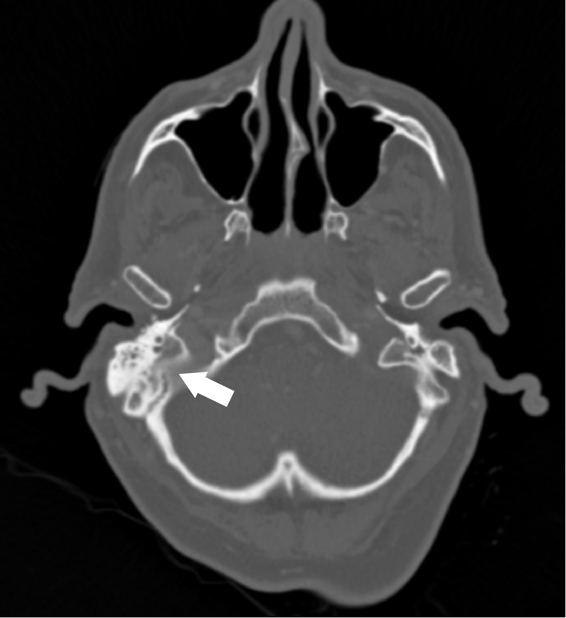

A 62 year old male with unknown past medical history was dropped off at the emergency department by EMS after being found altered with concern for IV drug use. On presentation he was febrile to 104.5o F, tachycardic, and although he was initially responsive, his mental status deteriorated. Labs were drawn and broad-spectrum antibiotic coverage with vancomycin, cefepime, and metronidazole was initiated in the ED. He then had a tonic-clonic seizure event and was given intravenous levetiracetam. A CT brain showed a right inferior temporal lobe lesion, initially interpreted as likely glioblastoma multiforme, causing subfalcine and uncal herniation. MRI revealed a ring-enhancing mass measuring 3 cm x 3 cm x 3 cm in the right temporal lobe with significant surrounding edema. CT of the temporal bones also revealed right mastoiditis (Figures 1 and 2).

Figure 2. CT of temporal bones with IV contrast demonstrating opacification of the right mastoid air cells and abnormal soft tissue within the epitympanum (arrow).